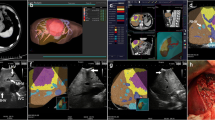

Preoperative liver surgery simulation

The two-dimensional (2D) CT patient images were transferred to a workstation (SYNAPSE VINCENT: FUJIFILM Medical Co., Ltd., Tokyo, Japan), and the authors (Y. O. and K.N.) generated the 3D images. We were able to perform a virtual hepatectomy in a preoperative operation meeting with the surgical team. The choice of resection was made based on tumor size, tumor location, liver function (ICGR 15, Child–Pugh classification) and surgical margins as determined by virtual hepatectomy (Fig. 2). We brought these 3D images of the liver into the operating room, and the surgical team could view the simulation images on a large-screen display during the actual hepatectomy.

A case of segment 8 segmentectomy. A 3D image was generated from patient CT DICOM data using a 3D image analysis system. A large tumor located in segment 8 of the liver is shown (a). S8 segmentectomy was planned, and the resection line was drawn along the demarcation line of P8 (b). An image of the resected liver (c). The position of the stump of P8 and the running directions of the middle hepatic vein and the right hepatic vein were similar to those determined in the preoperative simulation (d)